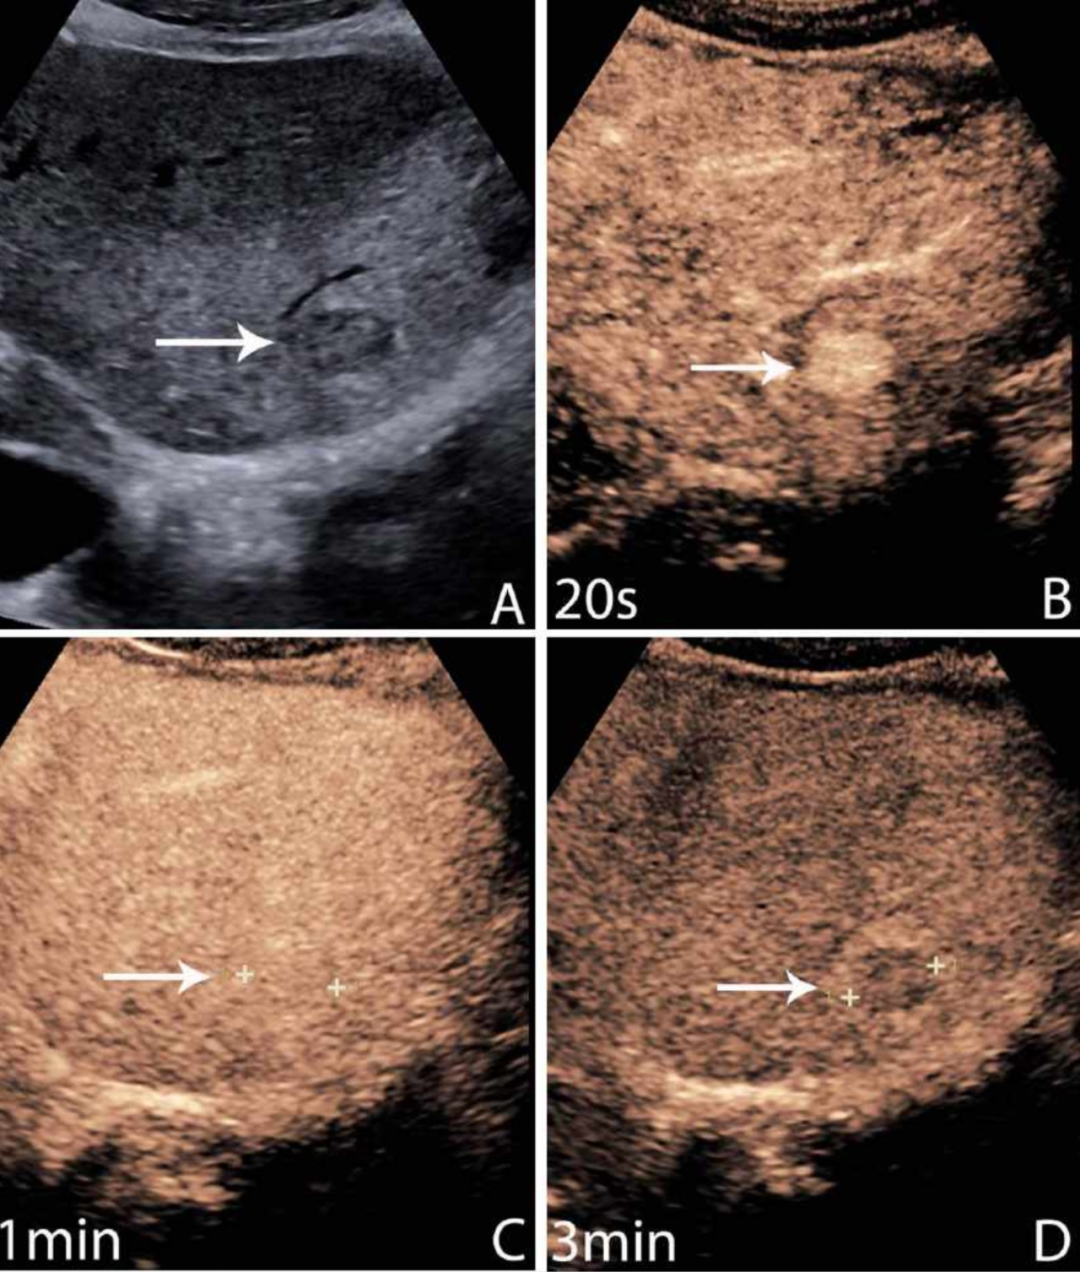

△ 与常规超声相比,肝脏病变的对比增强超声图像显示了不同时间点的动态增强模式

研究显示,超声造影在鉴别肝脏良恶性病变方面的敏感性高达93%,特异性达90%。这一诊断准确率与CT和MRI相当,但具有实时成像、无辐射、成本低廉等独特优势。

△ 对比增强超声图像显示肝脏局灶性病变随时间的动态增强,超声造影剂在肝脏诊断的成像过程